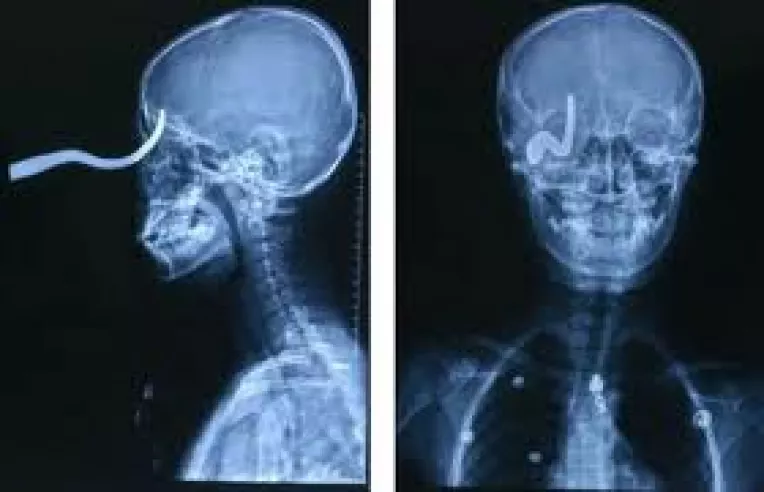

Dezbateri la televiziune cu oameni trepanati, fara creier, care au cip-uri implantate